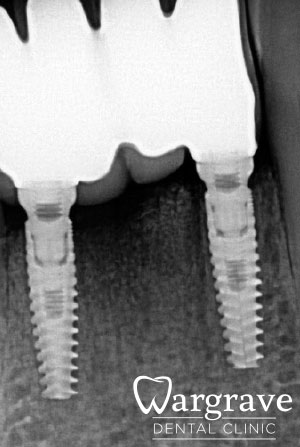

After

In this case the patient’s lower incisors had lost 60-70% of their supporting bone. The four failed incisors were extracted and replaced with a 4 unit implant bridge supported by two implants

All stages of surgical and restorative work by Mr RS Khurana